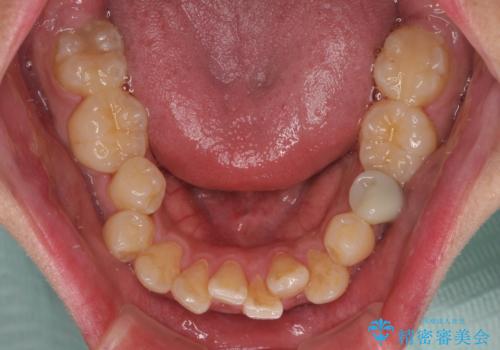

- 「歯並び全体のデコボコをきれいに整えたい」とのご希望で、20代男性の患者様が来院されました。

特に前歯部の叢生(歯の重なり)が強く、見た目だけでなく歯磨きのしにくさも気にされていました。

診査の結果、上下前歯に強い叢生が認められ、歯をきれいに並べるためのスペースが明らかに不足していました。

無理に歯を並べると、前歯が前方に突出するため、抜歯によるスペース確保が必要と判断しました。